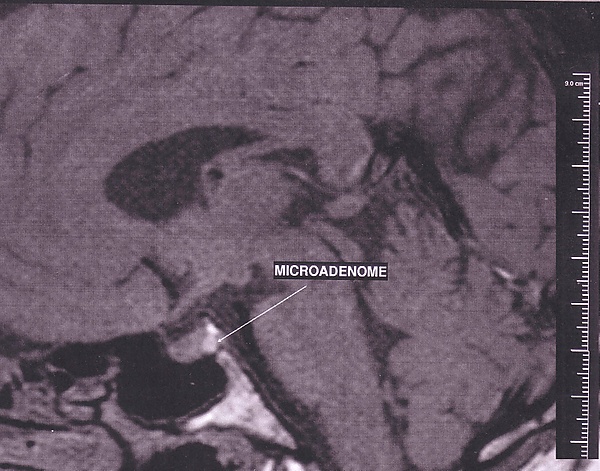

Классифицируют аденомы и по направленности роста. Рост определяется по отношению к турецкому седлу. На ранних этапах возникают эндоселлярные, то есть те, которые растут в полости седла. По мере роста происходит распространение опухоли ниже с достижением клиновидной пазухи, что переводит опухоль в вид инфраселлярного новообразования. При росте вверх формируется супраселлярная опухоль, кзади — ретроселлярная, в стороны — латеральная, кпереди — антеселлярная. Если опухоль растёт в нескольких направления, её название формируется из названий тех направлений, по которым наблюдается её рост. По размерам различают микроаденомы и макроаденомы.

МРТ является основным методом визуализации аденом гипофиза. У МРТ с КУ чувствительность достигает 90 %. Постконтрастные изображения и особенно изображения после динамического КУ являются неотъемлемой частью протокола МР-исследования гипофиза и значительно повышают диагностическую точность. Однако иногда морфологические изменения могут быть видны и на бесконстрастных изображениях. К ним относятся изменение железы со стороны аденомы, истончение и ремоделирование нижней стенки турецкого седла, а также отклонение воронки гипофиза от аденомы[2].

- на Т1 аденомы обычно изоинтенсивны по отношению к гипофизу;

- Т1-КУ:

- на динамических последовательностях — округлая область сниженного усиления по сравнению с остальной частью железы;

- на отсроченных изображениях картина варьирует от гипоусиления (наиболее распространённый вариант) до изоинтенсивности по сравнению с остальной частью железы, до гиперинтенсивности.

- Т2 — картина различная, однако в общем — небольшая гиперинтенсивность.

Очень важно помнить следующий факт при МР-исследовании гипофиза: достаточно распространены небольшие инциденталомы гипофиза, причём примерно в 2-30 % случаев при аутопсии выявляются небольшие бессимптомные микроаденомы.